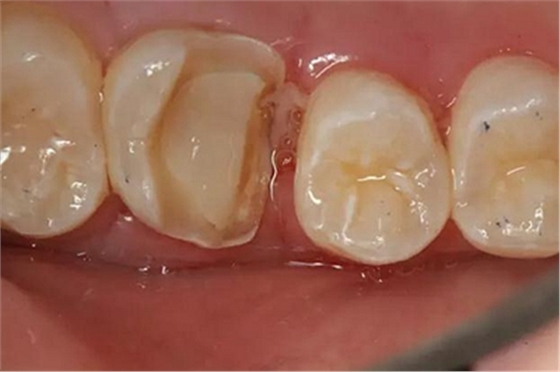

硅橡膠取模后,灌注模型,科爾琥珀樹脂制作嵌體。

一周后拆線,口內(nèi)試戴合適,粘結(jié)嵌體。